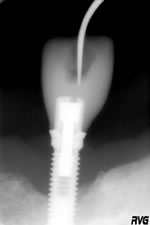

L’implant est stabilisé et il y a une reconstitution osseuse (R23 - 18_01_05)

R23 - 18_01_05